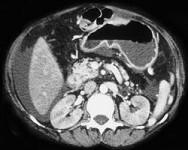

问题 如图,银染色可见系膜区及毛细血管袢有淀粉样物质沉积,刚果红染色呈砖红色阳性,电镜以淀粉样纤维沉积为特点,其病理诊断可考虑为 ( )

选项 A.糖尿病肾病 B.高血压肾损害 C.肾淀粉样变性 D.乙肝相关性肾炎 E.肾小球肾炎

答案 C